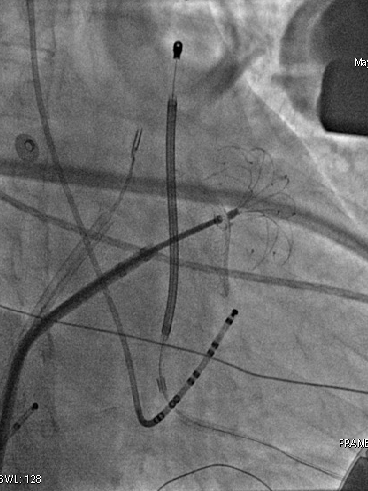

第一阶段手术

手术在全麻下进行,采用两切口植入技术。在经过X光片正位和左侧位确认后,标记能够获得最大心室除颤面积的导线和机壳所在位置并且划线,囊袋切口和剑突旁切口以及隧道,于囊袋切口切开皮肤6-7cm,逐层分离皮下组织至深筋膜层,制作前锯肌和背阔肌之间的肌间囊袋,保证足够的空间容纳装置并且装置位于肌间。按照标记的剑突旁切口切开皮肤3-4cm分离至筋膜层,通过皮下隧道导引针制作剑突至囊袋隧道,撤除导引针保留鞘管,将皮下除颤电极从鞘管穿出到剑突切口,撤除鞘管固定电极;再用另一个隧道针沿着既定路线制作胸骨上隧道,撤出隧道针,将皮下电极送入保留的鞘管,最后撕除鞘管。对所有伤口区进行有效止血,同时通过冲洗清洁所有切口,通过按摩将隧道内空气排出,避免因为空气残留导致的误放电。随后连接装置,置入囊袋内,逐层缝合皮下组织和皮肤,术区纱布覆盖,包扎,弹力绷带加压包扎止血。

术中行DFT测试, 65J一次除颤成功。